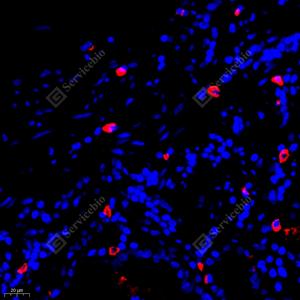

IF检测GLP1蛋白(货号 YB11346)(红色). 样品: 人胃, 4%多聚甲醛 (货号Y1112) 固定12-24小时. 抗原修复: Tris-EDTA抗原修复液(pH 9.0) (Y1214), 98℃, 20分钟. 封闭: 3% BSA(货号YC305021)的PBS溶液, 室温孵育30分钟. —抗: 1: 500稀释, 4℃ 孵育过夜. 二抗: Cy3标记山羊抗兔IgG (H+L) (货号YB21314), 1: 300稀释, 室温孵育1小时. |

IF检测GLP1蛋白(货号 YB11346)(红色). 样品: 大鼠胰腺, 4%多聚甲醛 (货号Y1112) 固定12-24小时. 抗原修复: Tris-EDTA抗原修复液(pH 9.0) (Y1214), 98℃, 20分钟. 封闭: 3% BSA(货号YC305021)的PBS溶液, 室温孵育30分钟. —抗: 1: 500稀释, 4℃ 孵育过夜. 二抗: Cy3标记山羊抗兔IgG (H+L) (货号YB21314), 1: 300稀释, 室温孵育1小时. |